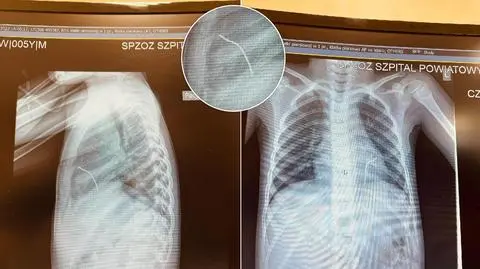

- Kawałek drutu przeszedł idealnie między żebrami, przeszedł przez śródpiersie i wbił się w lewą komorę serca, zatrzymując się na przeponie - opowiada dr Marek Kopala, kierownik kliniki kardiochirurgii w "Matce Polce".

Rodziców zaalarmowało to, że po pewnym czasie dziecko zaczęło sinieć i słabnąć. Pięciolatek został przewieziony karetką do szpitala w Opocznie, gdzie wykonano zdjęcie rentgenowskie. A na nim - jak opowiadał w rozmowie z tvn24.pl pełniący wtedy obowiązki lekarz Paweł Banaszek - długi na kilka centymetrów cień metaliczny w sercu. Chłopczyk został stamtąd śmigłowcem przetransportowany do "Matki Polki" w Łodzi. Szybka diagnoza być może uratowała życie dziecka.

Drut wbił się w lewą komorę serca chłopca